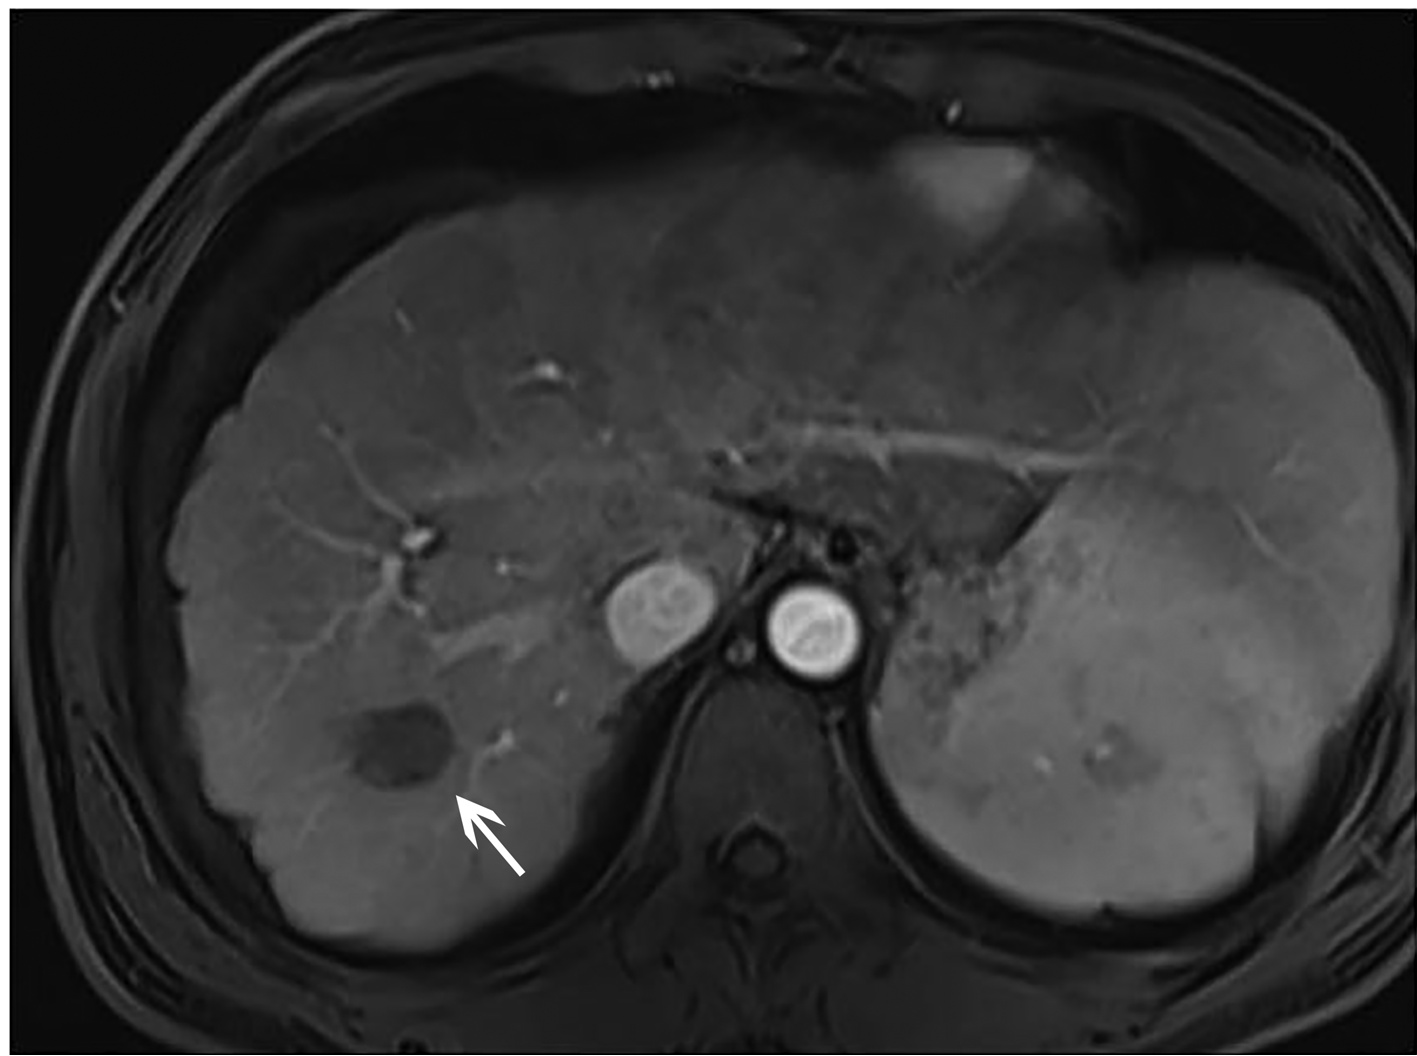

IgG4-related retroperitoneal fibrosis: A case report

Zhaoxia LI, Yang LIU, Nan LI, Zhuhui JI, Guijie XIN

2022, 38(5): 1126-1128. DOI: 10.3969/j.issn.1001-5256.2022.05.030

Abstract(758) HTML (364) PDF (2161KB)(55)

Abstract: